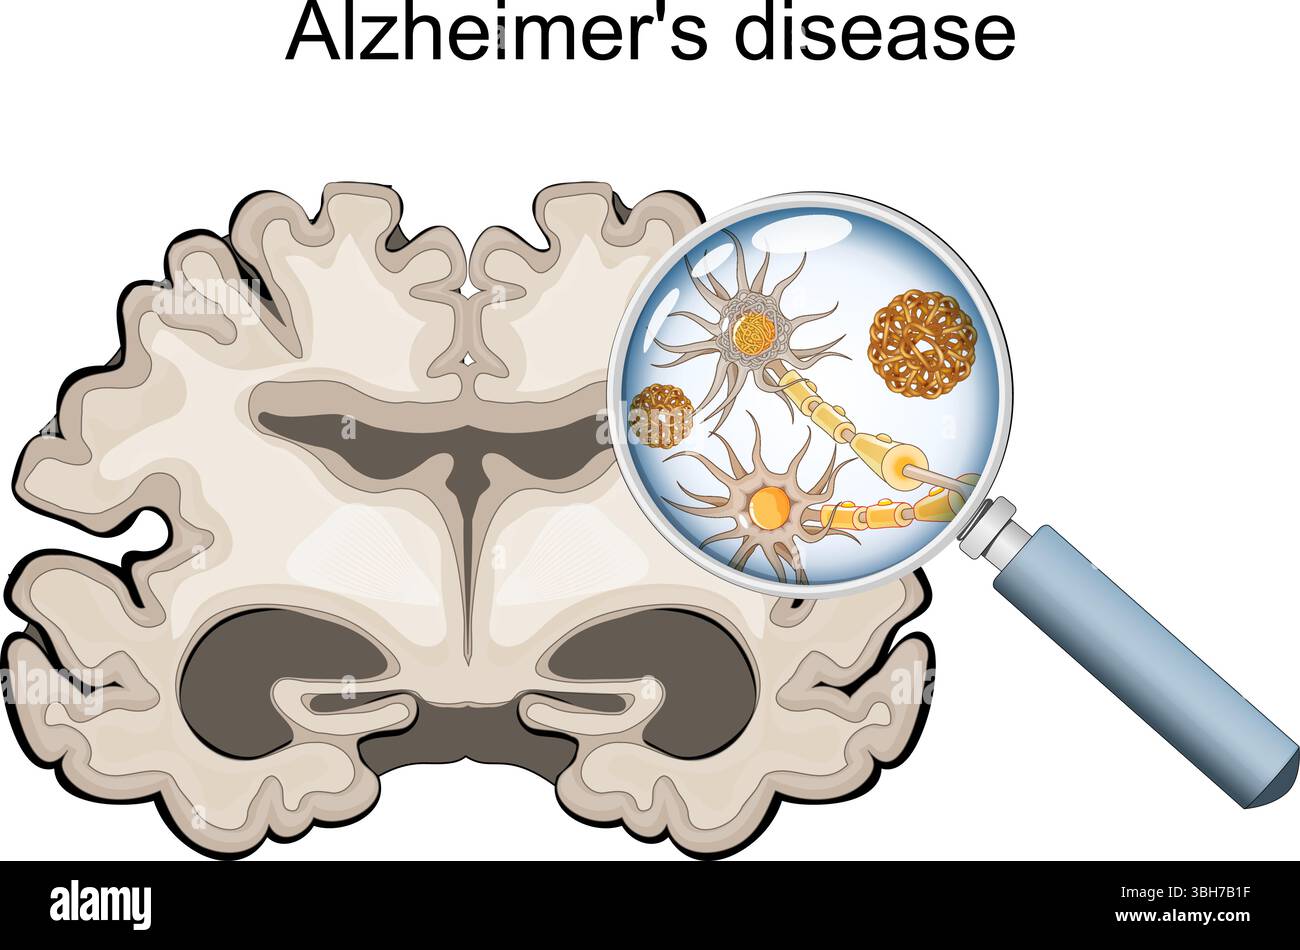

RF3BH7B1F–Morbo di Alzheimer. Neurodegenerazione. Sezione trasversale del cervello di Alzheimer, con atrofia della corteccia cerebrale, ventricoli ingrossati e ippocampo. Un